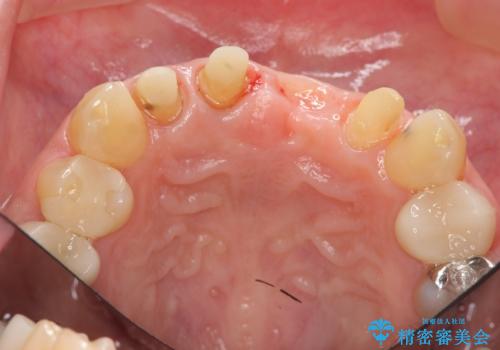

不良インプラントを除去し最終的にブリッジによる補綴で審美性の改善を行うこと、その準備として骨の造成・歯肉の移植による歯の欠損部顎堤のボリュームを維持・増大を計画します。

感染したインプラントからは排膿が間欠的に認められ、掻爬・除去が検討されうるような状況でした。

より審美的な改善を強く求められたため、インプラントを除去し可及的に欠損部顎堤を増大したのちブリッジによる審美改善を行いました。